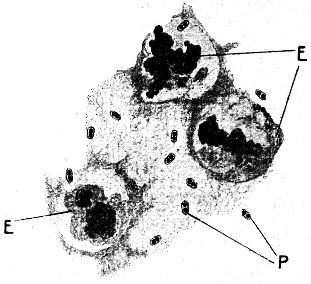

Bei einer beschränkten Zahl von Bakterienarten dient noch ein anderer sehr merkwürdiger Vorgang der Erhaltung der Art – nicht eigentlich der Fortpflanzung: es ist dies die bei manchen Stäbchenarten unter bestimmten Bedingungen vorkommende Bildung von sogenannten Sporen, eigentümlichen, durch ihr Aussehen und ihre besonderen Eigenschaften in gleicher Weise von den Bakterienzellen unterschiedenen Gebilden. Im ungefärbten Zustand, z. B. im hängenden Tropfen, fallen diese Sporen durch ihren starken Glanz auf: sie besitzen ein viel stärkeres Lichtbrechungsvermögen als die Bakterienzellen; ihre Anordnung ist bei verschiedenen Arten verschieden, aber bei jeder sporenbildenden Bakterienart charakteristisch. Bei einzelnen Arten bilden sie sich im Innern des Stäbchens (Endosporen), bei anderen Arten treten sie regelmäßig an den Enden auf (endständige Sporen; vgl. Abb. 7). Die Bildung dieser Sporen geht in der Weise vor sich, daß zunächst kleine stärker lichtbrechende Körnchen in dem Bakterienkörper auftreten, die dann an Größe zunehmen und schließlich die ganze Dicke der Bakterienzelle einnehmen, ja übertreffen können. Die Bakterienzelle selbst pflegt schließlich zu zerfallen, so daß nur die freie Spore übrig bleibt (vgl. Abb. 7 c). Bei Färbung mit den gewöhnlichen Anilinfarben bleiben die Sporen im Gegensatz zu dem Bakterienkörper[18] ungefärbt. Die hervorstechendste Eigentümlichkeit dieser Sporen ist ihre ganz außerordentlich große Widerstandsfähigkeit gegenüber allen möglichen physikalischen Einflüssen, denen die Bakterienzellen selbst erliegen. So vertragen sie viel höhere Grade der Austrocknung als jene, vor allem aber auch sehr viel stärkere Erhitzung, ohne abzusterben. Sie bleiben z. B. beim einmaligen Aufkochen einer Flüssigkeit am Leben und besitzen nun die weitere Fähigkeit, unter geeigneten Bedingungen wieder zu Bakterienzellen auszukeimen, die sich entweder durch Spaltung vermehren oder unter anderen Bedingungen wieder durch Sporenbildung gegen den Untergang schützen können. Sporenbildende Bakterien sind es z. B., die in der einmal kurz aufgekochten Milch nicht mit anderen zugrunde gehen, und sie sind denn auch die letzte Ursache der Irrlehre von der »generatio spontanea« gewesen (vgl. o.).